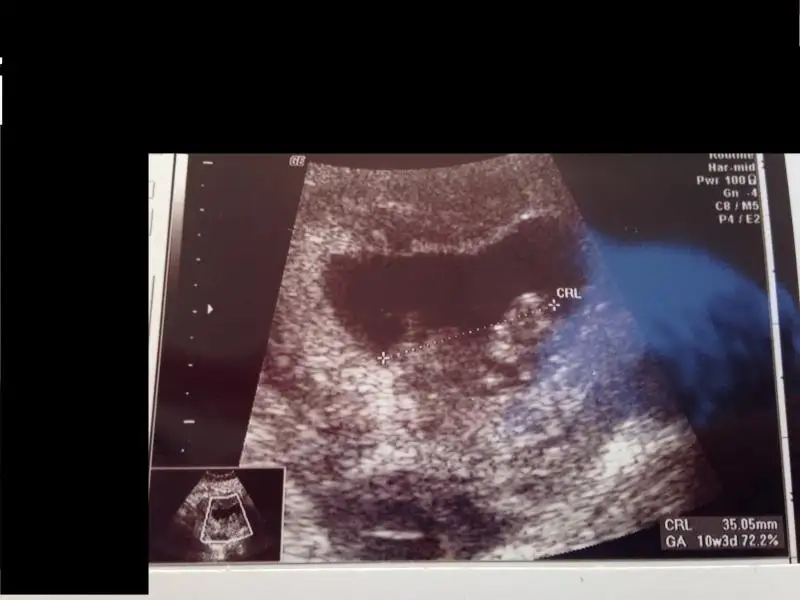

Bizim daha yeni, şuan 10+3 günümüz. 9+6 iken aşağıdaki şekildeydi durumumuz. Herhangi bir yorum yapabilen olurmu acaba :)

selam kızlar. Bugün kontrolümüz vardı minnağım kocaman olmuş el ayak sallar hale gelmiş :) 10+1 dik ama 2 gün önde gidiyor benimki 1 aydır o yüzden 10+3 ölçüyor usg. Fotoda nub gözükecek şekilde çıkmamış ama ben yinede bir şansımı deniyim kızlardan bir tahmin almaya çalışıyım dedim. Doktorum cinsiyet tahmini için 1,5 ay sonra dedi kim beklicek okadr çatlarım ben :) Bakın bakalım bişiler görebilecekmisiniz canlarım :16: